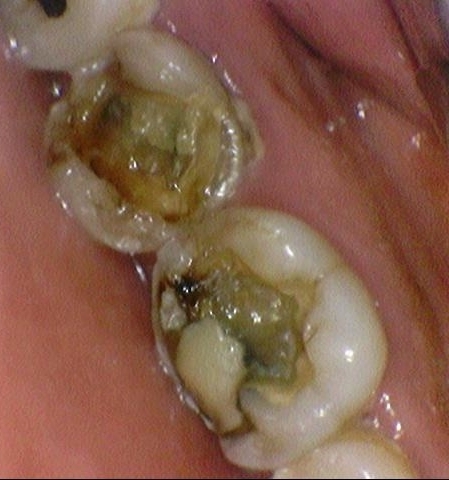

CASE 2. 미용적 목적 + 충치치료를 위한 지르코니아 크라운

[환자분께서 사진 공개에 동의하셨습니다]

환자분 방문 목적 자체가 미용적인 목적이었고,

금이나 보기 싫은 부분은 제거를 원하셨기 때문에

타 치과에서 오래 전에 한 PFM크라운, 골드 인레이 등을

뜯어내고 넓은 부위의 충치 제거 후 지르코니아 크라운을 씌우셨습니다.

↓ 치료 후

색상도 본인 치아보다 밝게 하면서, 금도 보이지 않아 더 깨끗한 치아로 보일 수 있게 합니다.